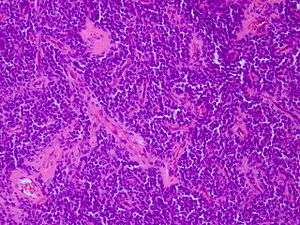

Micrograph of an H&E stained section of a peripheral PNET.

The peripheral PNET (pPNET) is now thought to be virtually identical to Ewing sarcoma:

"Current evidence indicates that both Ewing's sarcoma and PNET have a similar neural phenotype and, because they share an identical chromosome translocation, they should be viewed as the same tumor, differing only in their degree of neural differentiation. Tumors that demonstrate neural differentiation by light microscopy, immunohistochemistry, or electron microscopy have been traditionally labeled PNETs, and those that are undifferentiated by these analyses have been diagnosed as Ewing's sarcoma."[3]